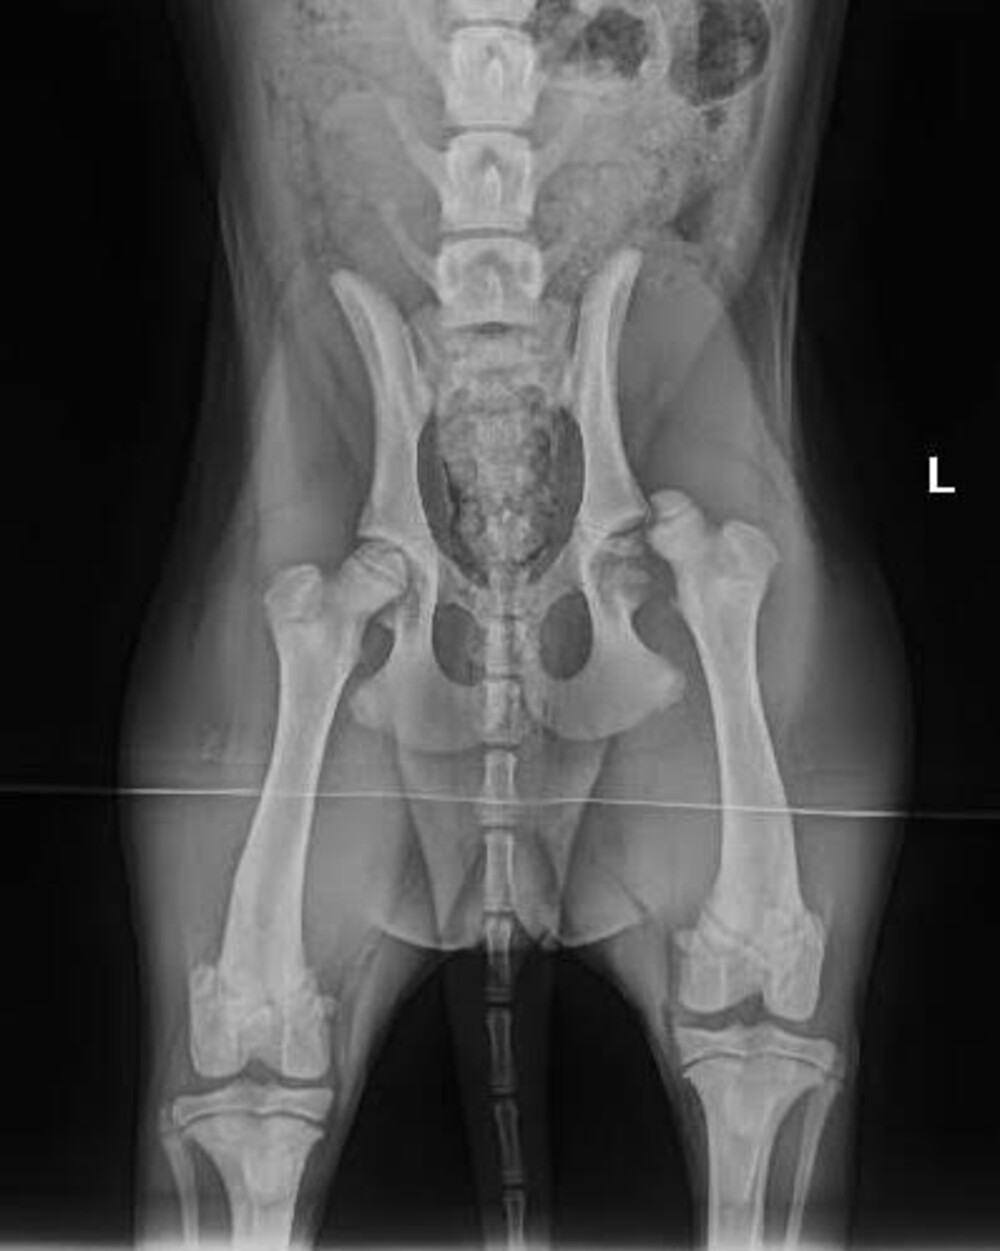

Gevolg; heup uit de kom en een stukje afgebroken vd kop van de femur.

Op aandringen van ons (eerst dachten ze dat het alleen gekneusd was) en de dierenarts zijn er foto’s gemaakt en is ze gisteren onder het mes gegaan en is er een nieuwe kop geplaatst.